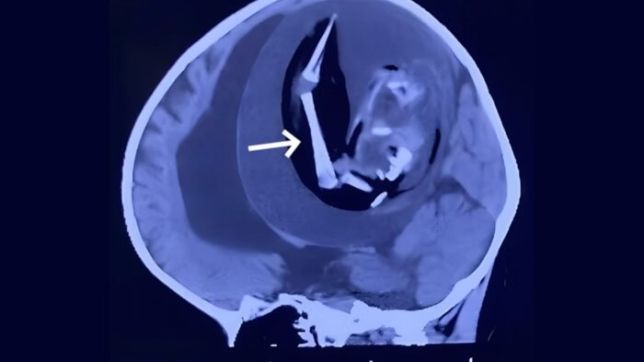

Em uma ressonância, os médicos viram a cápsula que as defesas do corpo da menina tinha feito ao redor do feto e pensaram se tratar de um tumor de grandes proporções. Exames mais detalhados, porém, apontaram a presença de ossos, indicando que se tratava de um feto mal-formado.

Como ele estava comprimindo o cérebro da bebê, levando à uma hipertensão craniana, foi feita uma cirurgia para retirada do feto. Este é o único tratamento possível para casos de FIF. Os médicos descobriram que além do gêmeo parasita, vários tumores se desenvolveram ao redor de onde estava o feto.